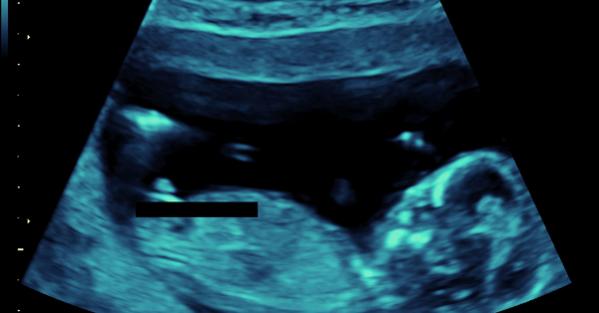

I guess boy!!

looks like a:xy:!!

Boy!!!!

:BabyBoy: